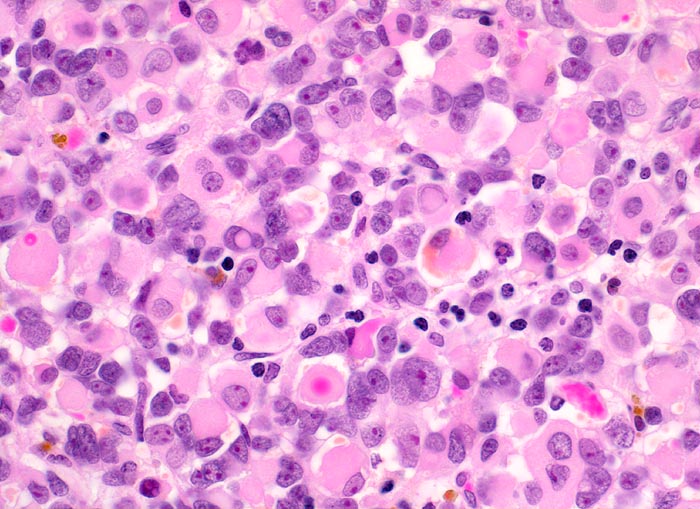

Das makroskopische Bild ist uncharakteristisch und variiert in Abhängigkeit von der Lokalisation. Fokale Nekrosen und zystische Degeneration sind häufig. Es werden verschiedene histologische Subtypen unterschieden, welche charakteristische molekulargenetische Aberrationen aufweisen und mit unterschiedlichen Prognosen assoziiert sind. Die beste Prognose haben botryoide und spindelzellige Rhabdomyosarkome gefolgt von embryonalen Rhabdomyosarkomen (intermediäre Prognose) und alveolären bzw. pleomorphen Rhabdomyosarkomen (schlechteste Prognose). Therapieantwort und Prognose hängen neben der Histologie auch von der Lokalisation ab. Embryonale Rhabdomyosarkome zeigen ein breites morphologisches Spektrum. Dieses reicht von wenig differenzierten Tumoren, die nur mittels Immunhistochemie und Elektronenmikroskopie diagnostizierbar sind zu gut differenzierten Tumoren, die fetaler Muskulatur ähneln. Oft findet sich eine Mischung von wenig differenzierten kleinen, runden und/oder spindeligen Zellen und eine variable Anzahl differenzierter Rhabdomyoblasten mit reichlich eosinophilem Zytoplasma. Die Rhabdomyoblasten können rund, spindelig, kaulquappenförmig oder spinnwebenförmig sein. Besser differenzierte Zellen enthalten reichlich Zytoplasma mit Querstreifung, welche allerdings teilweise nur elektronenmikroskopisch nachweisbar ist.

• Dieser besteht aus mesenchymalen Zellen mit unterschiedlicher Ausdifferenzierung.

• Die am wenigsten ausdifferenzierten Zellen zeigen wenig amphophiles Zytoplasma und ovale Kerne.

• Dominierend sind in diesem Tumor teils mehrkernige Rhabdomyoblasten mit reichlich eosinophilem Zytoplasma und exzentrischem Zellkern. Die Querstreifung des Zytoplasmas ist in der HE Färbung nur andeutungsweise erkennbar.

• "Spinnwebenzellen" mit peripheren Zytoplasmavakuolen.